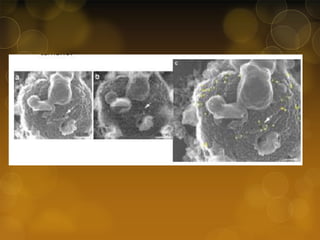

Ultrastructure of spiral and types A and

B coccoid forms of H. pylori. (a) SEM of

spiral forms on day 1. Flagella are seen

on one side of the cells (arrows). A

spherical organism is visible (asterisk).

Bar, 2 μm. Inset: TEM of a spiral form.

A flagellum (arrow) and an

intracytoplasmic granule (arrowhead)

are visible. Bar, 0.5 μm. (b) SEM of type

A coccoid forms on day 3 in CLM. Cells

are spherical with an irregular surface

and possess few flagella. They have a

tendency to adhere to each other. Bar, 2

μm. Inset: TEM of type A coccoid form.

The surface is sunken (arrowhead).

Membrane and intracytoplasmic

structures are not clearly visible. Bar,

0.5 μm. (c) SEM of type B coccoid forms

on day 3 in 300 mM-LM. The smooth

surface is tightly encircled by flagella

(arrowheads). Bar, 2 μm. Inset: TEM of

type B coccoid form. The membrane

structure is well preserved and a

flagellum is also visible (arrowhead).

Bar, 0.5 μm.